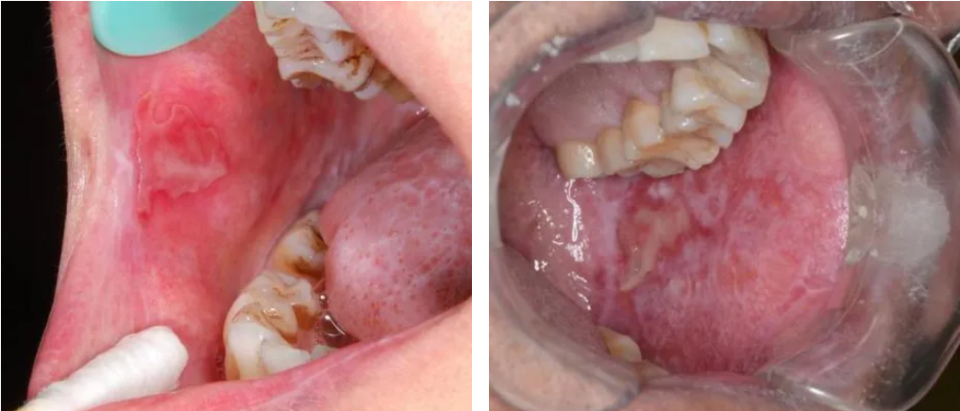

2、口干与吞咽困难

当cGVHD累及腺体,导致类似干燥综合征的腺体萎缩和功能障碍时,患者会出现唾液分泌质与量的双重下降3、5。据统计,约65.4%的患者受口干困扰7,唾液缺失不仅导致口腔黏膜干燥、灼痛,更使得吞咽食物困难,严重者可导致营养摄入不足和体重下降。唾液保护功能的丧失,直接增加了猛性龋和口腔念珠菌病的风险5。此外,累及口腔小涎腺导管可导致导管阻塞,进而在黏膜表面形成小涎腺囊肿,多见于硬腭后部,亦常伴疼痛或咀嚼、吞咽不适9-10。

口干表现(图片源自陶人川教授团队)

黏液囊肿表现(图片源自陶人川教授团队)